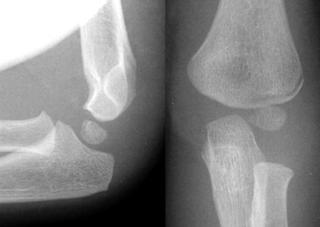

Fractura multisegmentara intertrohanteriana Fractura Salter - Harris I

Fractura Salter - Harris I Fractura Salter - Harris II

Fractura Salter - Harris III

Fractura Salter - Harris IV Fractura Salter - Harris V